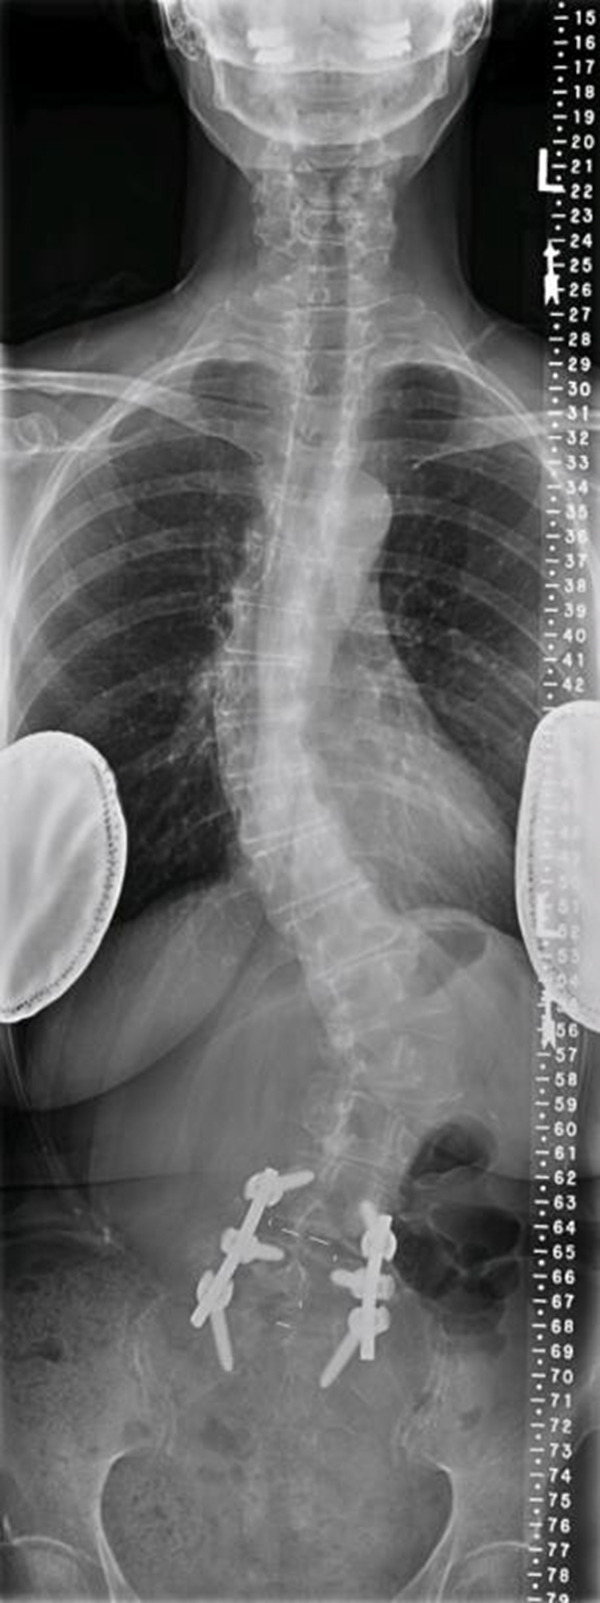

术后X线

51岁,女性,腰椎术前矢状位明显失平衡,术后多年加重;

期望解决下肢痛及站立问题。

术前X线